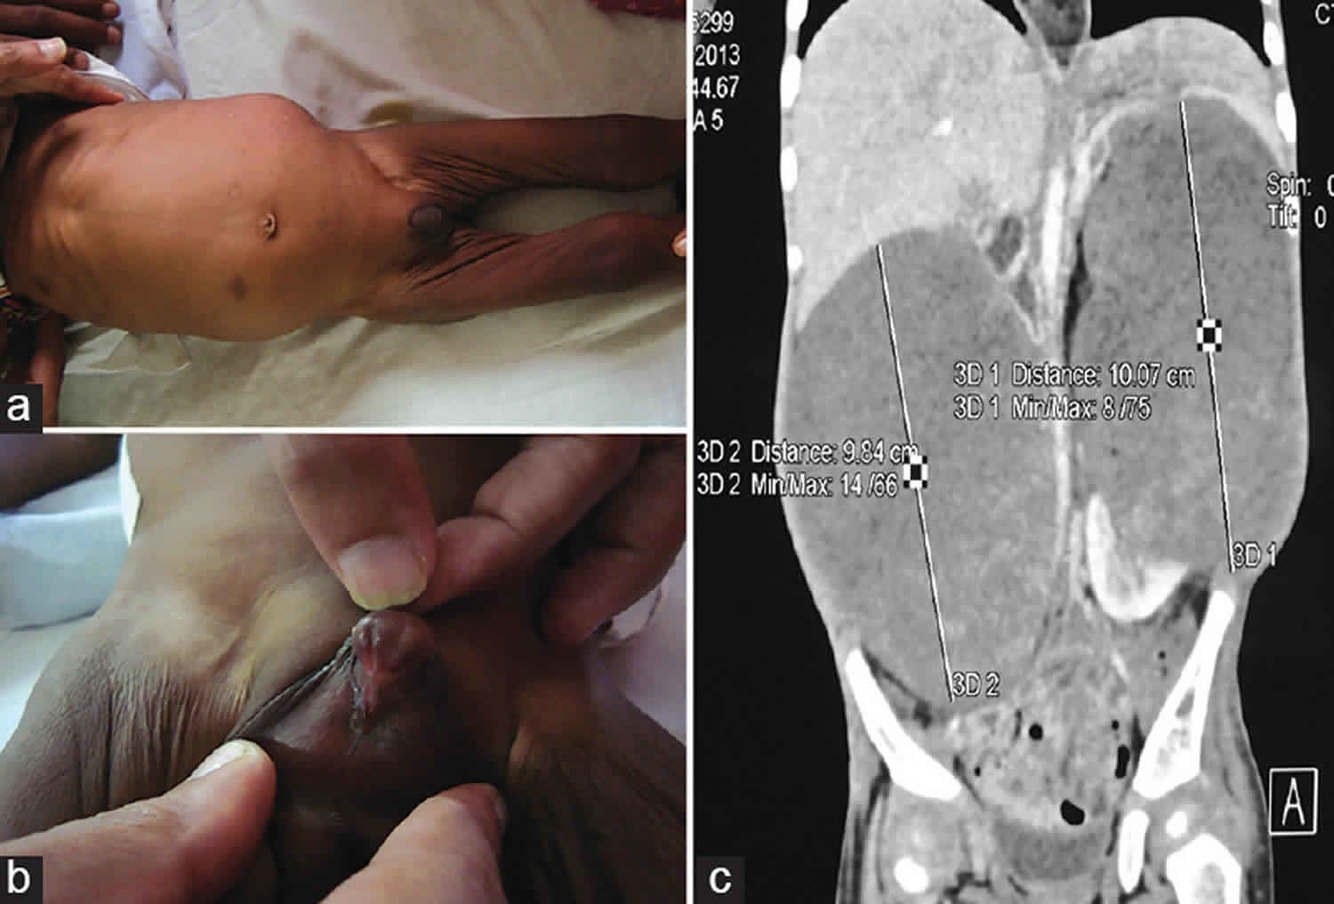

Macroglossia, hemihypertrophy, omphalocele

BECKWITH WIEDEMANN SYNDROME

Clinical Features: Polyhydramnios, LGA baby, Macroglossia, Abdominal wall defects (omphalocele), pre-auricular ear creases/pits, renal abnormalities, hemi-hypertrophy, hyperplasia of organs, renal abnormalities, neoplasms (Wilms, adrenal carcinoma, hepatoblastoma)

Investigations: Chromosomal microarray

Monitoring: